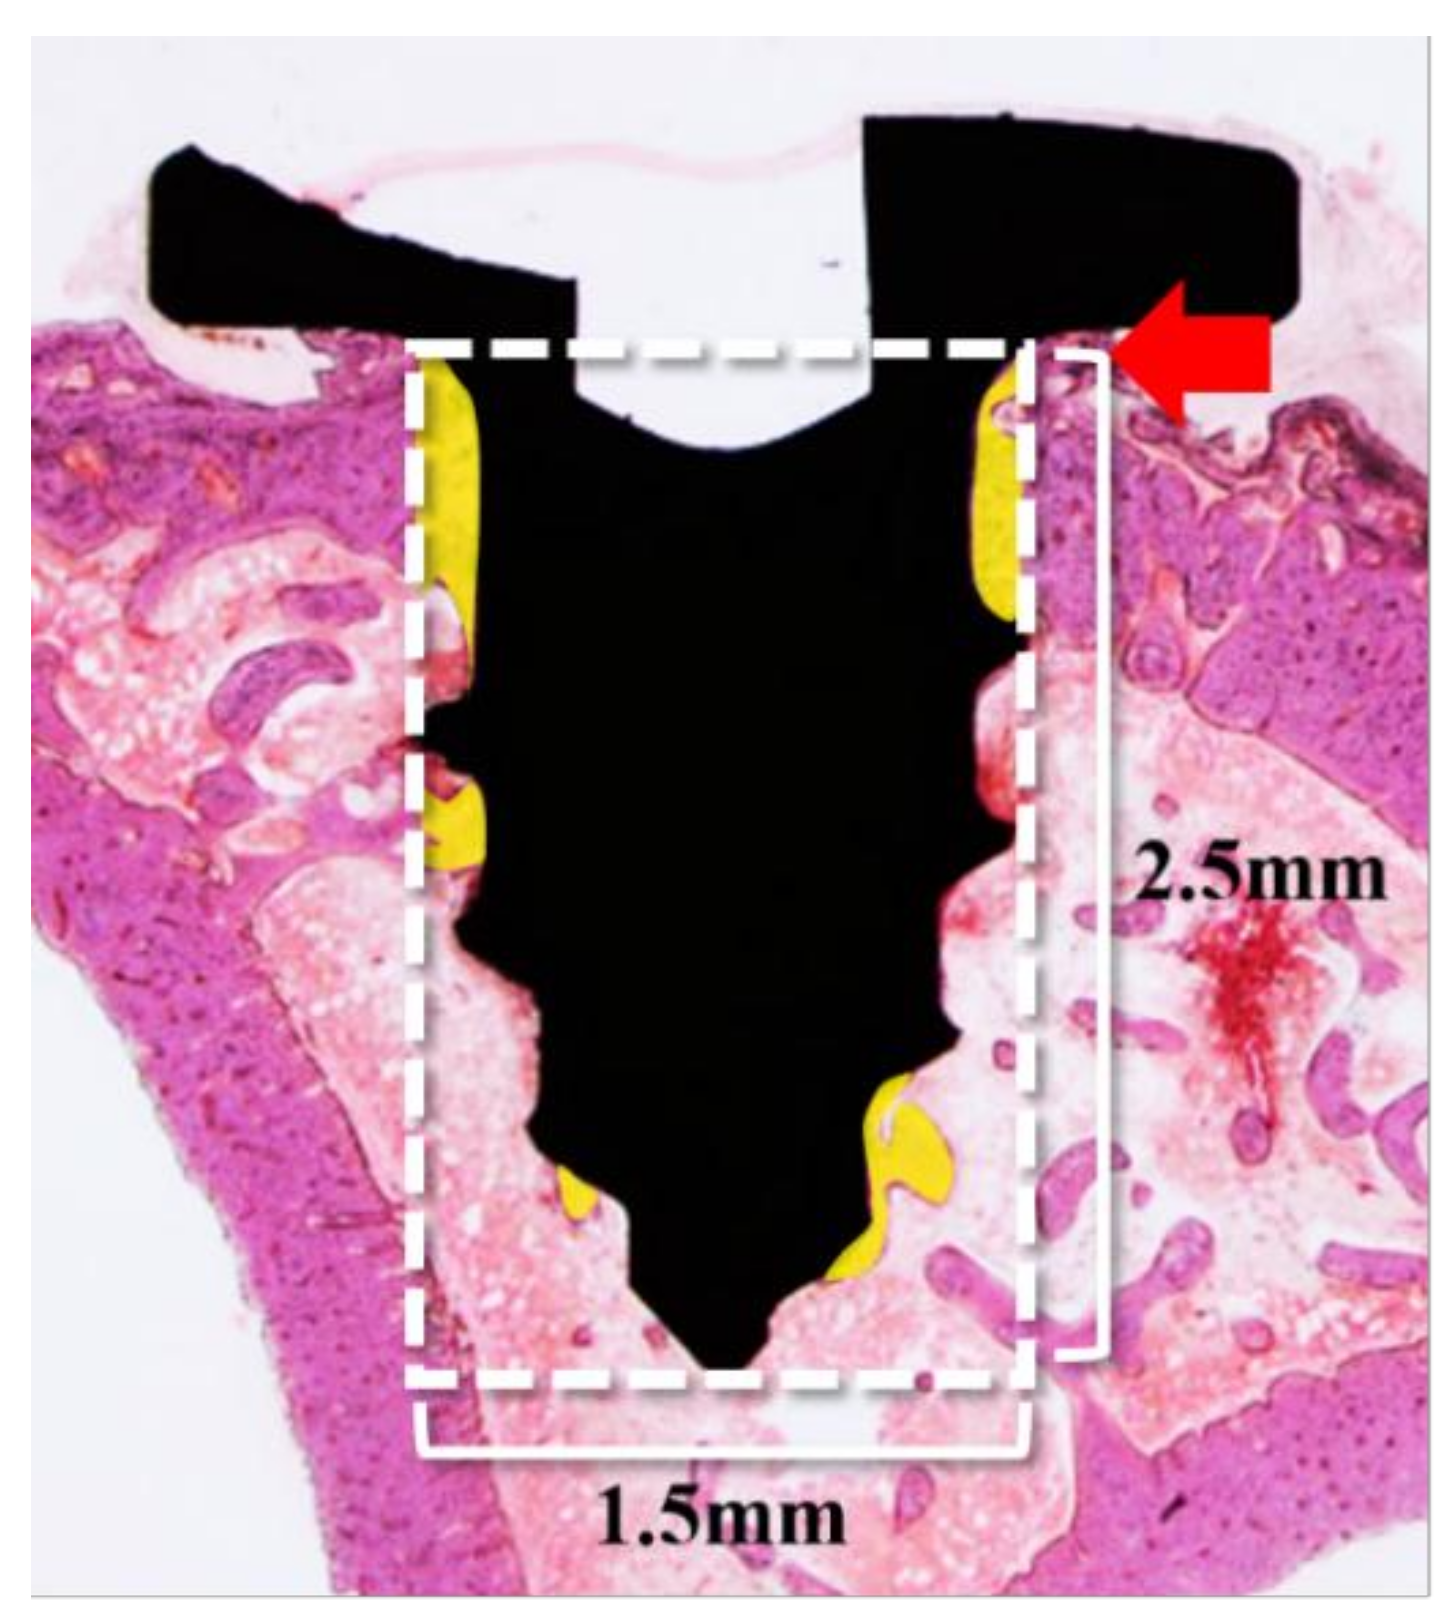

2.2.4. Histometric Findings

4.3.4. Histology Analysis